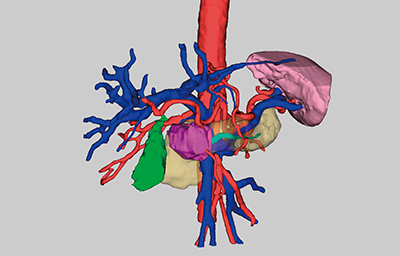

しかし,実際に3D表示を作成する場合,3D構造が複雑な膵臓の抽出には多大な労力・時間が必要となり,膵臓の外科的切除の適応可否を検討するためにこの時間を捻出するのは,外科医にとって容易ではない。そこで,V6では,鏡視下シミュレータアプリケーションに,1クリックで膵臓を抽出する機能を実装している(図2)。このような複雑な形状の臓器抽出は,従来のルールベース的な機械学習法を用いた手法では,精度に限界があった。この問題の改善をねらい,本バージョンではディープラーニングを用いて設計した膵臓抽出機能に更新している。

図2 膵臓抽出の画像例

膵臓は形状が複雑であり,周囲に同じような輝度値を持つ臓器が隣接しているが,ディープラーニングを用いて設計した膵臓抽出機能により,膵臓を膵臓領域として認識する。